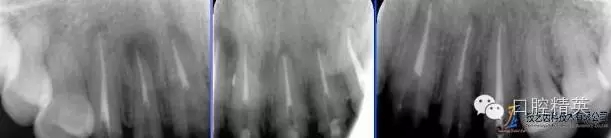

術(shù)前根尖片

術(shù)后根尖片